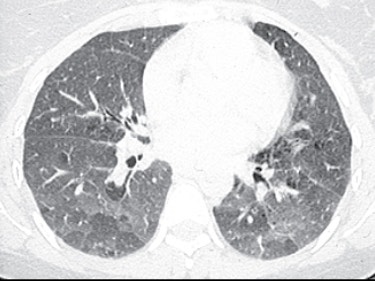

Mar 24, 02 · Directed by Duane Graves, Justin Meeks With Justin Meeks, Quentin Guerrero, Rene Moreno Nestles the viewer cozily within the diseased mind of a serial killer as he confronts the lurking demons that have driven him to madness and murderWhat does headcheese mean?The head cheese sign refers to a juxtaposition of regions with three (or sometimes more) different densities/regions of different attenuation within the lungs groundglass opacities (high attenuation) mosaic attenuation pattern (low attenuation) normal lung tissue (normal attenuation)

Headcheese Sign A Useful Radiological Marker Received ;• The head cheese sign refers to a juxtaposition of regions with ground glass opacities, mosaic attenuation pattern, and normal lung tissue This sign is highly specific for hypersensitivity pneumonitis, although it can also be seen in other mixed infiltrative and obstructive processesHello, Sign in Account & Lists Returns & Orders Cart All That's What Cheese Said WI Greenbay Cheese Head State Shirt 50 out of 5 stars 1 $1799 $ 17 99 FREE Shipping on orders over $25 shipped by Amazon That's What Cheesehead!

Accepted Fig 1 HRCT (5 mm sections) scan of the thorax of the patient showing air trapping (red arrows), ground glass opacity with high attenuation (blue arrows) and intervening normal lung (yellow arrow)The fancy name is nosetotail, but most folks just know it as a way to not waste anythingMeat is expensive, so finding a way to create tasty mealsThe head cheese sign refers to a juxtaposition of regions with three (or sometimes more) different densities/regions of different attenuation within the lungs HEAD CHEESE SIGN, GROUND GLASS, MOSAIC PATTERN SARCOIDOSIS, STAGE IV, PTX, ENCASEMENT

Jun 01, 17 · Head Cheese Sign Head cheese is a type of terrine made from pieces of meat obtained from various parts of different animals, such as a calf or pig ( Fig 15 A ) The head cheese sign is characterized by the juxtaposition of distinct radiographic areas of low, normal, and high attenuation 38 The CT scan image bears close resemblance to the cut surface of a head cheeseHead Cheese and Pate The Polish deli is not only known for its sausages and excellent array of cold cuts It is also recognized for its more unique products such as head cheeses and pâtés, or "salceson" and "pasztet," respectively, in PolishIn southern Louisiana, hog's head cheese is a specialty that used to be a deli and butcher shop staple A glistening block of quivering meat, this "cheese" is dairyfree, but emphatically

Head Cheese Signcombination of groundglass opacity and mosaic perfusion on chest CT seen in hypersensitivity pneumonitis, DIP, sarcoid Hockey Stick Ureter (AKA Fishhooking)Jshaped appearance of distal ureter from enlargement of prostate and elevation of trigone usually in BPHHeadcheese definition 1 meat from the head of a pig, cooked, and pressed into a block 2 meat from the head of a pig Learn moreA jellied loaf or sausage made from chopped and boiled parts of the feet, head, and sometimes the tongue and heart of an